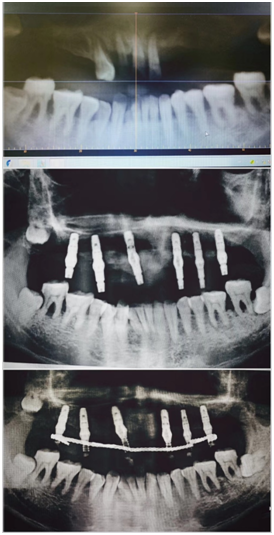

日前,晋江门诊部医护团队顺利完成了首例上半口即刻种植即刻修复手术。该患者李大哥今年39岁,因重度牙周炎导致上颌多颗牙脱落,上颌剩余的少少几颗牙也极度松动,无法保留,下颌剩余牙齿伴有不同程度的牙周问题。针对患者这类疑难复杂病例,门诊部种植团队医师专门进行病例分析和讨论,在与患者充分沟通后,医师团队建议李大哥进行牙周系统治疗后选择上半口即刻种植即刻修复手术。种植手术在9月6日上午8点开始,在医护团队的通力协作下,手术非常顺利,下午5点为患者安装了临时固定义齿,达到了预期的目标,患者感觉良好。该病例的成功完成提升了晋江门诊部医护团队的综合能力,说明了晋江门诊部医护团队解决种植疑难病例的能力迈上了新台阶。(供稿人:李杰森周勇 审核人:钟萍萍)